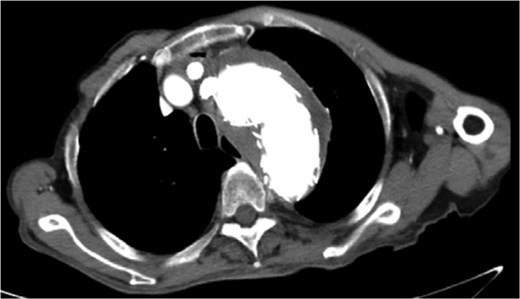

Despite recovery, the patient remained physically exhausted and required ongoing rehabilitation. In May 2023, after a COVID-19 infection, the patient experienced blood in phlegm. CTA confirmed successful aneurysm repair with no endoleak (Fig. 3). Thus the patient was hospitalized in the respiratory department. Relevant pulmonary examination indicators and lung CT results revealed no lung lesions associated with blood in sputum (Fig. 4). However, throughout July, 2023, intermittent blood in phlegm continued, and a CTA on July 19, 2023, revealed a type IV endoleak (Fig. 5). Conversely, aortography on July 27, 2023, showed no obvious endoleak. Closed drainage of the left thoracic cavity was performed, but blood in phlegm recurred on August 9, 2023. A Gore C-TAG stent graft was deployed in the thoracic aortic arch, with its proximal end anchored at the ostium of the left subclavian artery stent graft to ensure complete coverage of the endoleak site both proximally and distally(Fig. 6). Post-surgery, blood in phlegm symptoms abated.

In July 2023, endoleak was observed upon reexamination, possibly of stent graft origin.

The thoracic aorta was re-implanted with a covered stent graft to cover the breach.